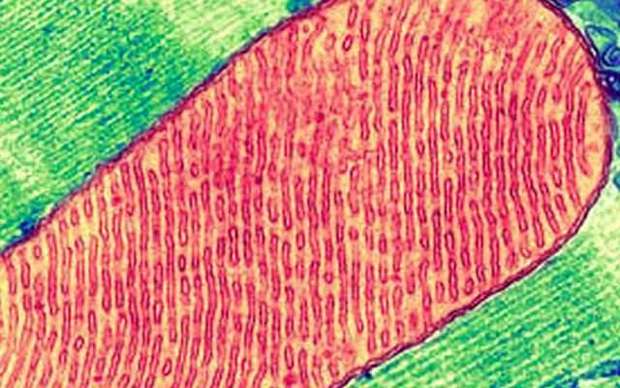

محققان روی یک تئوری وابسته به «واکنش خطر سلولی» یا CDR مطالعه می‌کنند که شامل واکنش طبیعی و جامع سلولی به آسیب‌ها و استرس‌هاست. آنها این تئوری را با ویژگی‌های متابولیکی سه مرحله CDR تشریح می‌کنند که چرخه درمان را هم شامل می‌شود. هدف آن کمک به حفاظت از سلول و شروع طوفانی فرآیند درمانی است که باعث سخت شدن غشاهای سلولی می‌شود. در سطح مولکولی، تعادل سلولی تغییر یافته و مانع از کامل شدن چرخه درمان می‌شود و در نتیجه شیوه واکنش سلول نسبت به جهان را برای همیشه تغییر می‌دهد. وقتی این اتفاق می‌افتد، سلول‌ها به گونه‌ای رفتار می کنند که با وجود سپری شدن مرحله خطر، گویی سلول‌ها هنوز آسیب‌دیدهد‌اند یا در مرحله خطر قرار دارند.